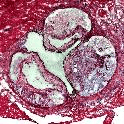

Our faculty involved in tissue engineering investigate areas such as bone, cartilage and cardiovascular regeneration, as well as regulation of cellular responses.